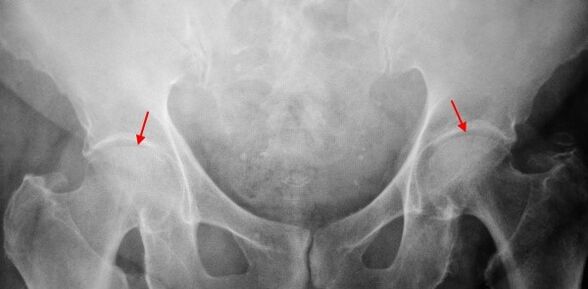

On the ray X of the patient suffering from 1st degree coxartrosis, mild changes are determined: a moderate irregular narrowing of the joint gap, as well as the bone growth around the external or internal edge of the acetabulum in the absence of changes from the head and neck of the femur.

In the X -ray images for the 2nd degree coxartrosis, a significant irregular narrowing of the joint gap (more than half of the normal height) is determined.The head of the femur is somehow moved upwards, deformed and increases in size and its contours become irregular.Bone growth with this degree of coxartrosis appear not only on the interior, but also on the outer edge of the acetabulum and go out of the cartilage.

A strong narrowing of the joint gap, a pronounced expansion of the head of the thigh and more bone outcrops, are detected on radiographs for coxarthrosis of the 3rd degree.

The diagnosis of coxartrosis is based on clinical signs and data of further studies, whose main is the radiography.In many cases, X -rays allow you to establish not only the degree of coxartrosis, but also the cause of its occurrence.Therefore, for example, an increase in the corner of the neck-diaphysal, the scenes and flattening of the acetabulum indicate dysplasia and the changes in the form of the proximal part of the femur are indicated that coks arthrosis is a consequence of the perties disease or youth epiphyphysiolisi.On the radiographs of patients with coxartrosis, it is possible to detect changes that indicate injuries.